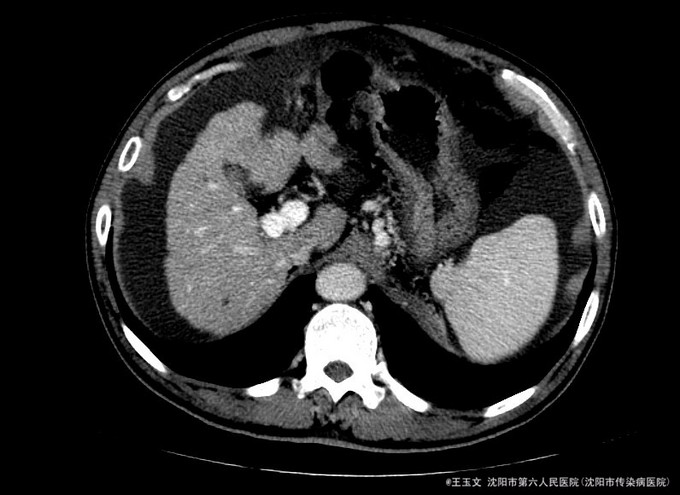

查体:神志清,巩膜无黄染,心肺听诊无异常,腹软,无压痛,肝区无叩痛,移动性浊音阳性,双下肢无浮肿,扑翼样震颤阴性。可见肝掌和腹水等阳性体征 化验结果:天门冬氨酸氨基转移酶 48 U/L、胆碱酯酶 3254 U/L、总蛋白 84.0 g/L、总胆红素 39.9 umol/L、非结合胆红素 26.7 umol/L。凝血酶原时间 15.5 秒、凝血酶原比率 1.35 、凝血酶原百分活动度 54.9 %、活化部分凝血酶原时间 40.7 秒、纤维蛋白原含量 1.255 g/L、D-二聚体 3.05 ug/ml↑。乙型肝炎病毒表面抗原 阳性(+) ↑、乙型肝炎病毒e抗体 阳性(+) ↑、乙型肝炎病毒核心抗体 阳性(+) 。甲胎蛋白(AFP) 11.52 ng/mL。 超声检查示:肝硬化,较多腹水,肝内见多个低回声,较大约1.5*1.0厘米,边界清晰。 肝增强ct:肝脏边缘欠规整,肝裂增宽,各叶大小比例失调,肝实质内见多个低密度结节,较大位于Ⅳ段,大小约2.04cm,增强扫描动脉期Ⅳ段两个结节中等强化,门脉期及延迟扫描呈低密度,余结节无明显强化;肝内亦见多个小囊性密度灶,较大约1.44cm,无强化。肝内外门静脉显示清晰,脾脏增大增厚,超过肝脏下缘,胆囊不大,壁增厚,其内密度均匀,胰腺形态密度无特殊。肝内外胆管未见明显扩张,腹膜后未见明显肿大淋巴结。食管下段胃底贲门区见扩张扭曲的血管影。肝周及腹膜间隙见有中等量液性密度影。

诊断:初步诊断:1、乙肝肝硬化 失代偿期; 确定诊断:乙肝肝硬化 活动性 失代偿期C-P B级 行肝脏增强CT后补充诊断:肝占位性位病变 行DSA下肝动脉造影后修订诊断:原发性肝癌 治疗:限盐饮食,口服利尿剂,减少水钠储留,促进腹水消退,静点异甘草酸镁保肝治疗,行增强CT检查,发现肝内占位,考虑恶性可能大,患者肝功改善后,于局麻下DSA下行肝动脉造影及TACE治疗

术后患者未见TACE治疗并发症,无不适,复查化验结果:天门冬氨酸氨基转移酶 41 U/L、胆碱酯酶 1901 U/L、白蛋白 29.3 g/L、总胆红素 24.6 umol/L。甲胎蛋白测定:甲胎蛋白(AFP) 7.75 ng/mL。患者肝功改善,术后一周时候复查CT示病灶碘油沉积尚好,办理出院。 本例患者比较典型,虽然其术前甲胎蛋白不高,但其增强CT有典型的“快进快出”特征,并且乙肝背景,有经验的医师会考虑其为原发性肝癌的可能非常大, TACE治疗即可以确诊其肝癌,又能在确诊的同时给予治疗。